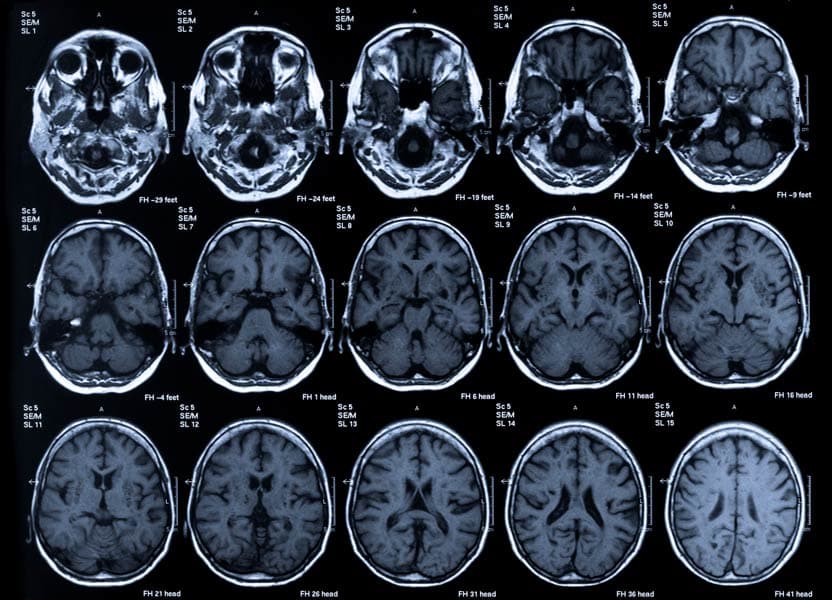

Early in her career, Rogalski operationalized the term “SuperAgers” to describe people over the age of 80 whose memory still functions as well as that of someone in their 50s or 60s. Rather than simply focusing on what goes wrong in dementias, she wants to understand what goes right in the brains of SuperAgers. She leads an international team whose research methods encompass a wide range of assessments, from cognitive and motor function tests to neuroimaging and wearable sensors. This deep phenotyping approach aims to understand the intricate factors contributing to healthy brain aging and dementia.